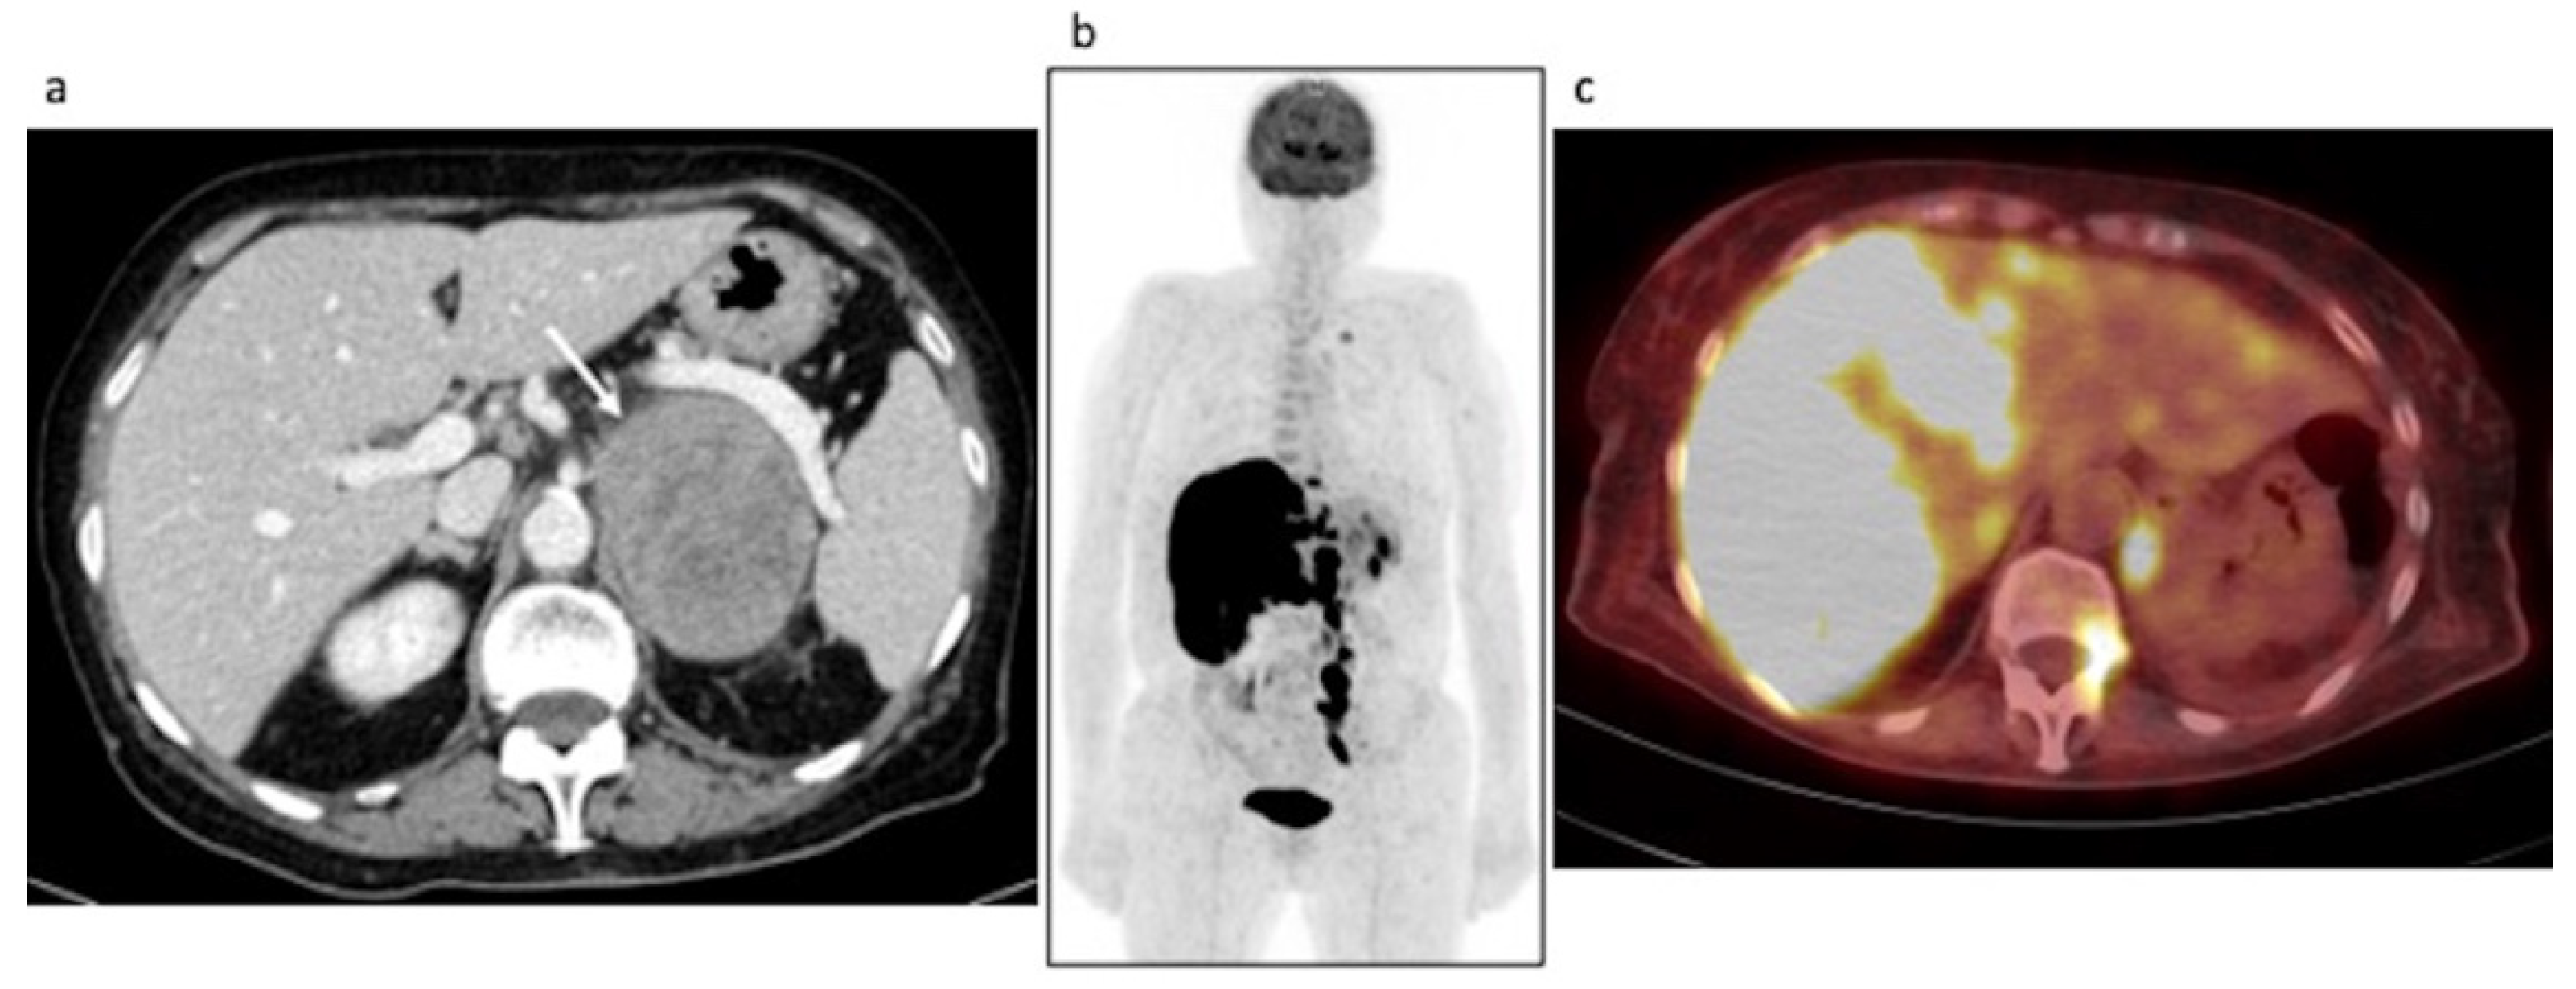

3.2.2. Restaging: Case #2